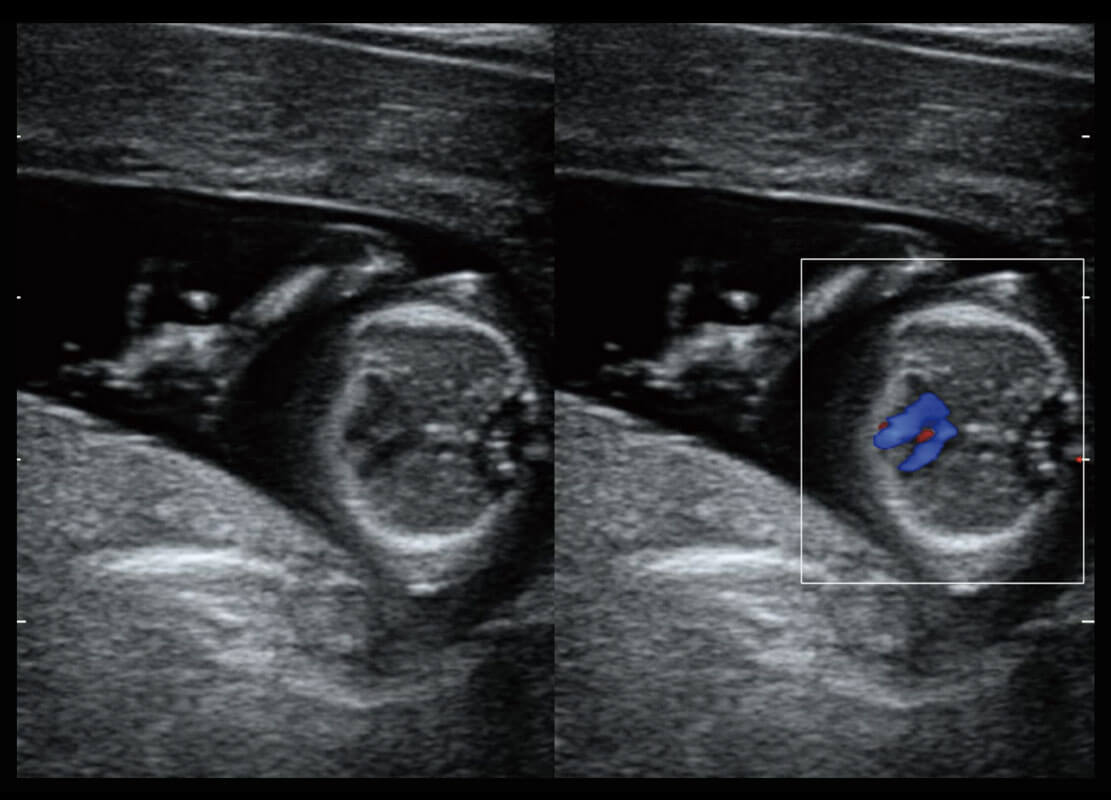

P60搭载一系列胎儿心脏成像技术,实现精细的胎儿心脏评估。

四腔心血流

胎心容积成像